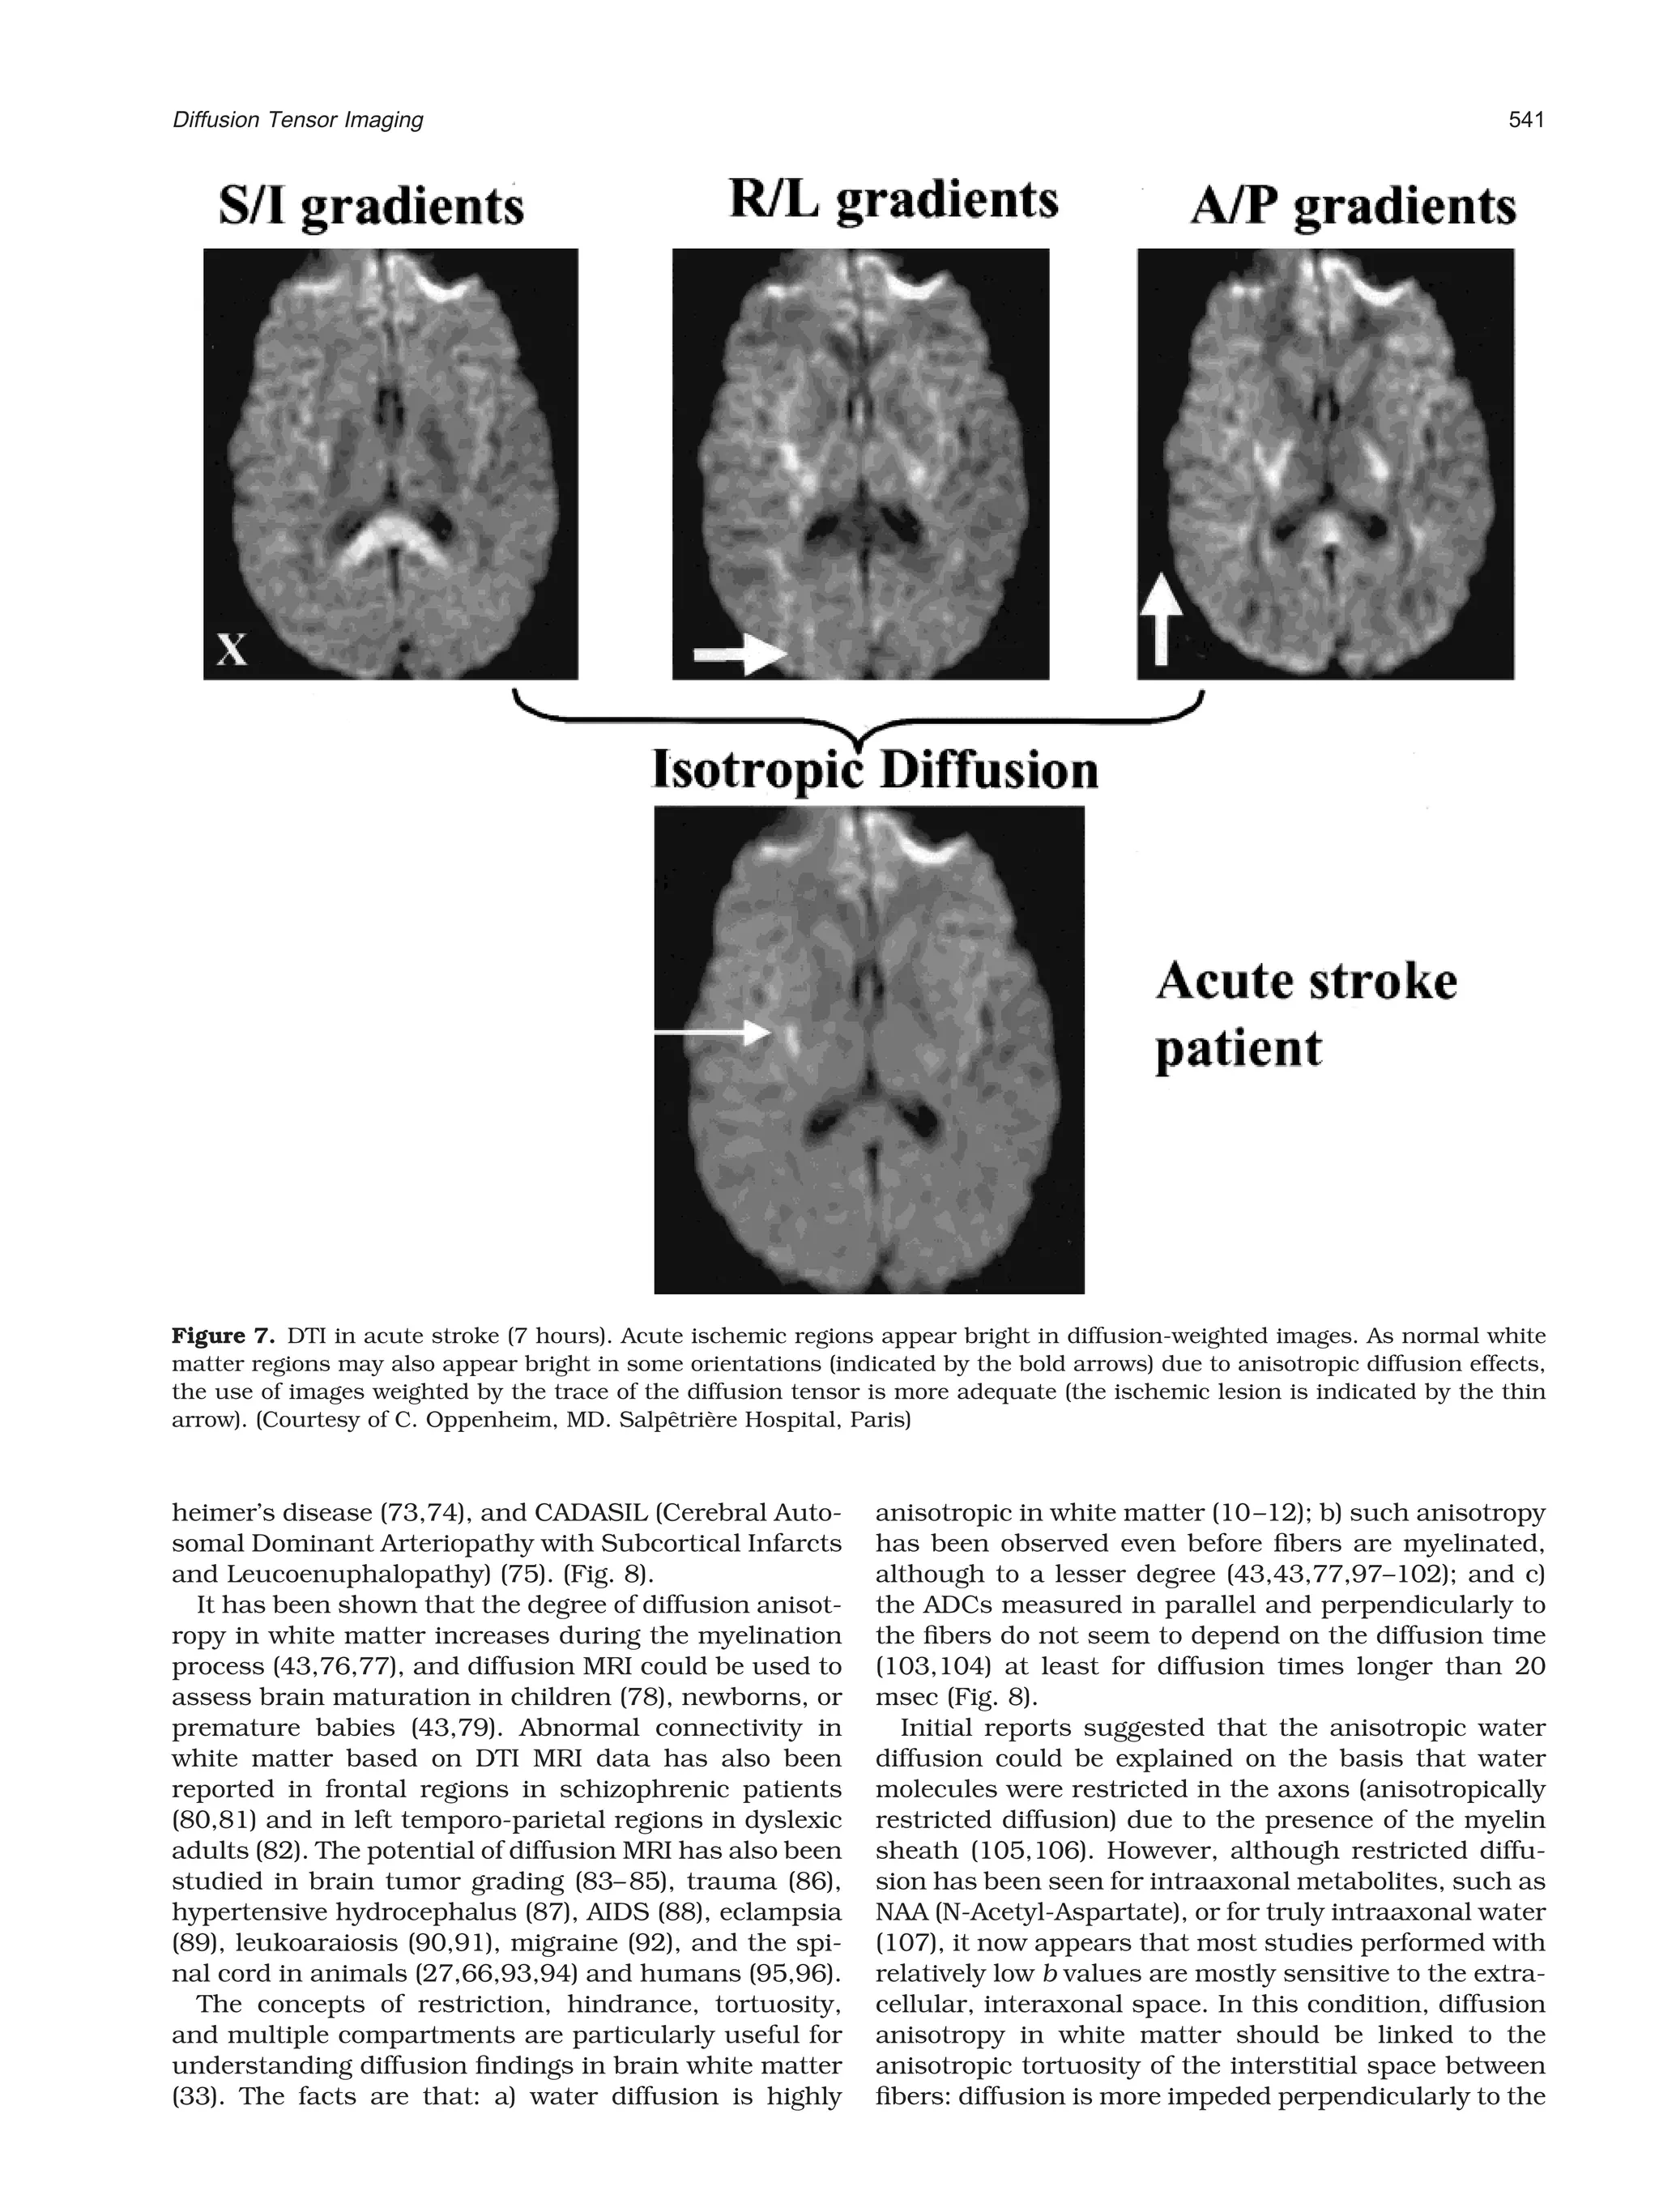

tropic diffusion effects in diffusion-weighted images

may sometimes mimic ischemic regions, especially near

ventricular cavities: if diffusion sensitization is made in

only one direction, which is perpendicular to the white

matter fibers, bright (low diffusion) spots will be visible

on the images. It is, therefore, a good practice to use

images of the mean diffusivity (or the trace of the diffu-

sion tensor) to remove these artifacts (34) (Fig. 7).

Figure 7. DTI in acute stroke (7 hours). Acute ischemic regions appear bright in diffusion-weighted images. As normal white

matter regions may also appear bright in some orientations (indicated by the bold arrows) due to anisotropic diffusion effects,

the use of images weighted by the trace of the diffusion tensor is more adequate (the ischemic lesion is indicated by the thin

arrow). (Courtesy of C. Oppenheim, MD. Salpetriere Hospital, Paris)